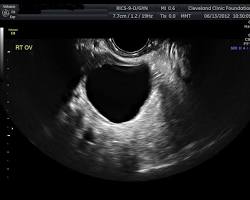

- To diagnose and monitor problems with the uterus, ovaries, and fallopian tubes: This includes conditions such as fibroids, ovarian cysts, pelvic inflammatory disease (PID), and endometriosis.

- To evaluate fertility: Pelvic ultrasounds can be used to assess the health of the eggs and follicles in the ovaries, as well as to check for blockages in the fallopian tubes.